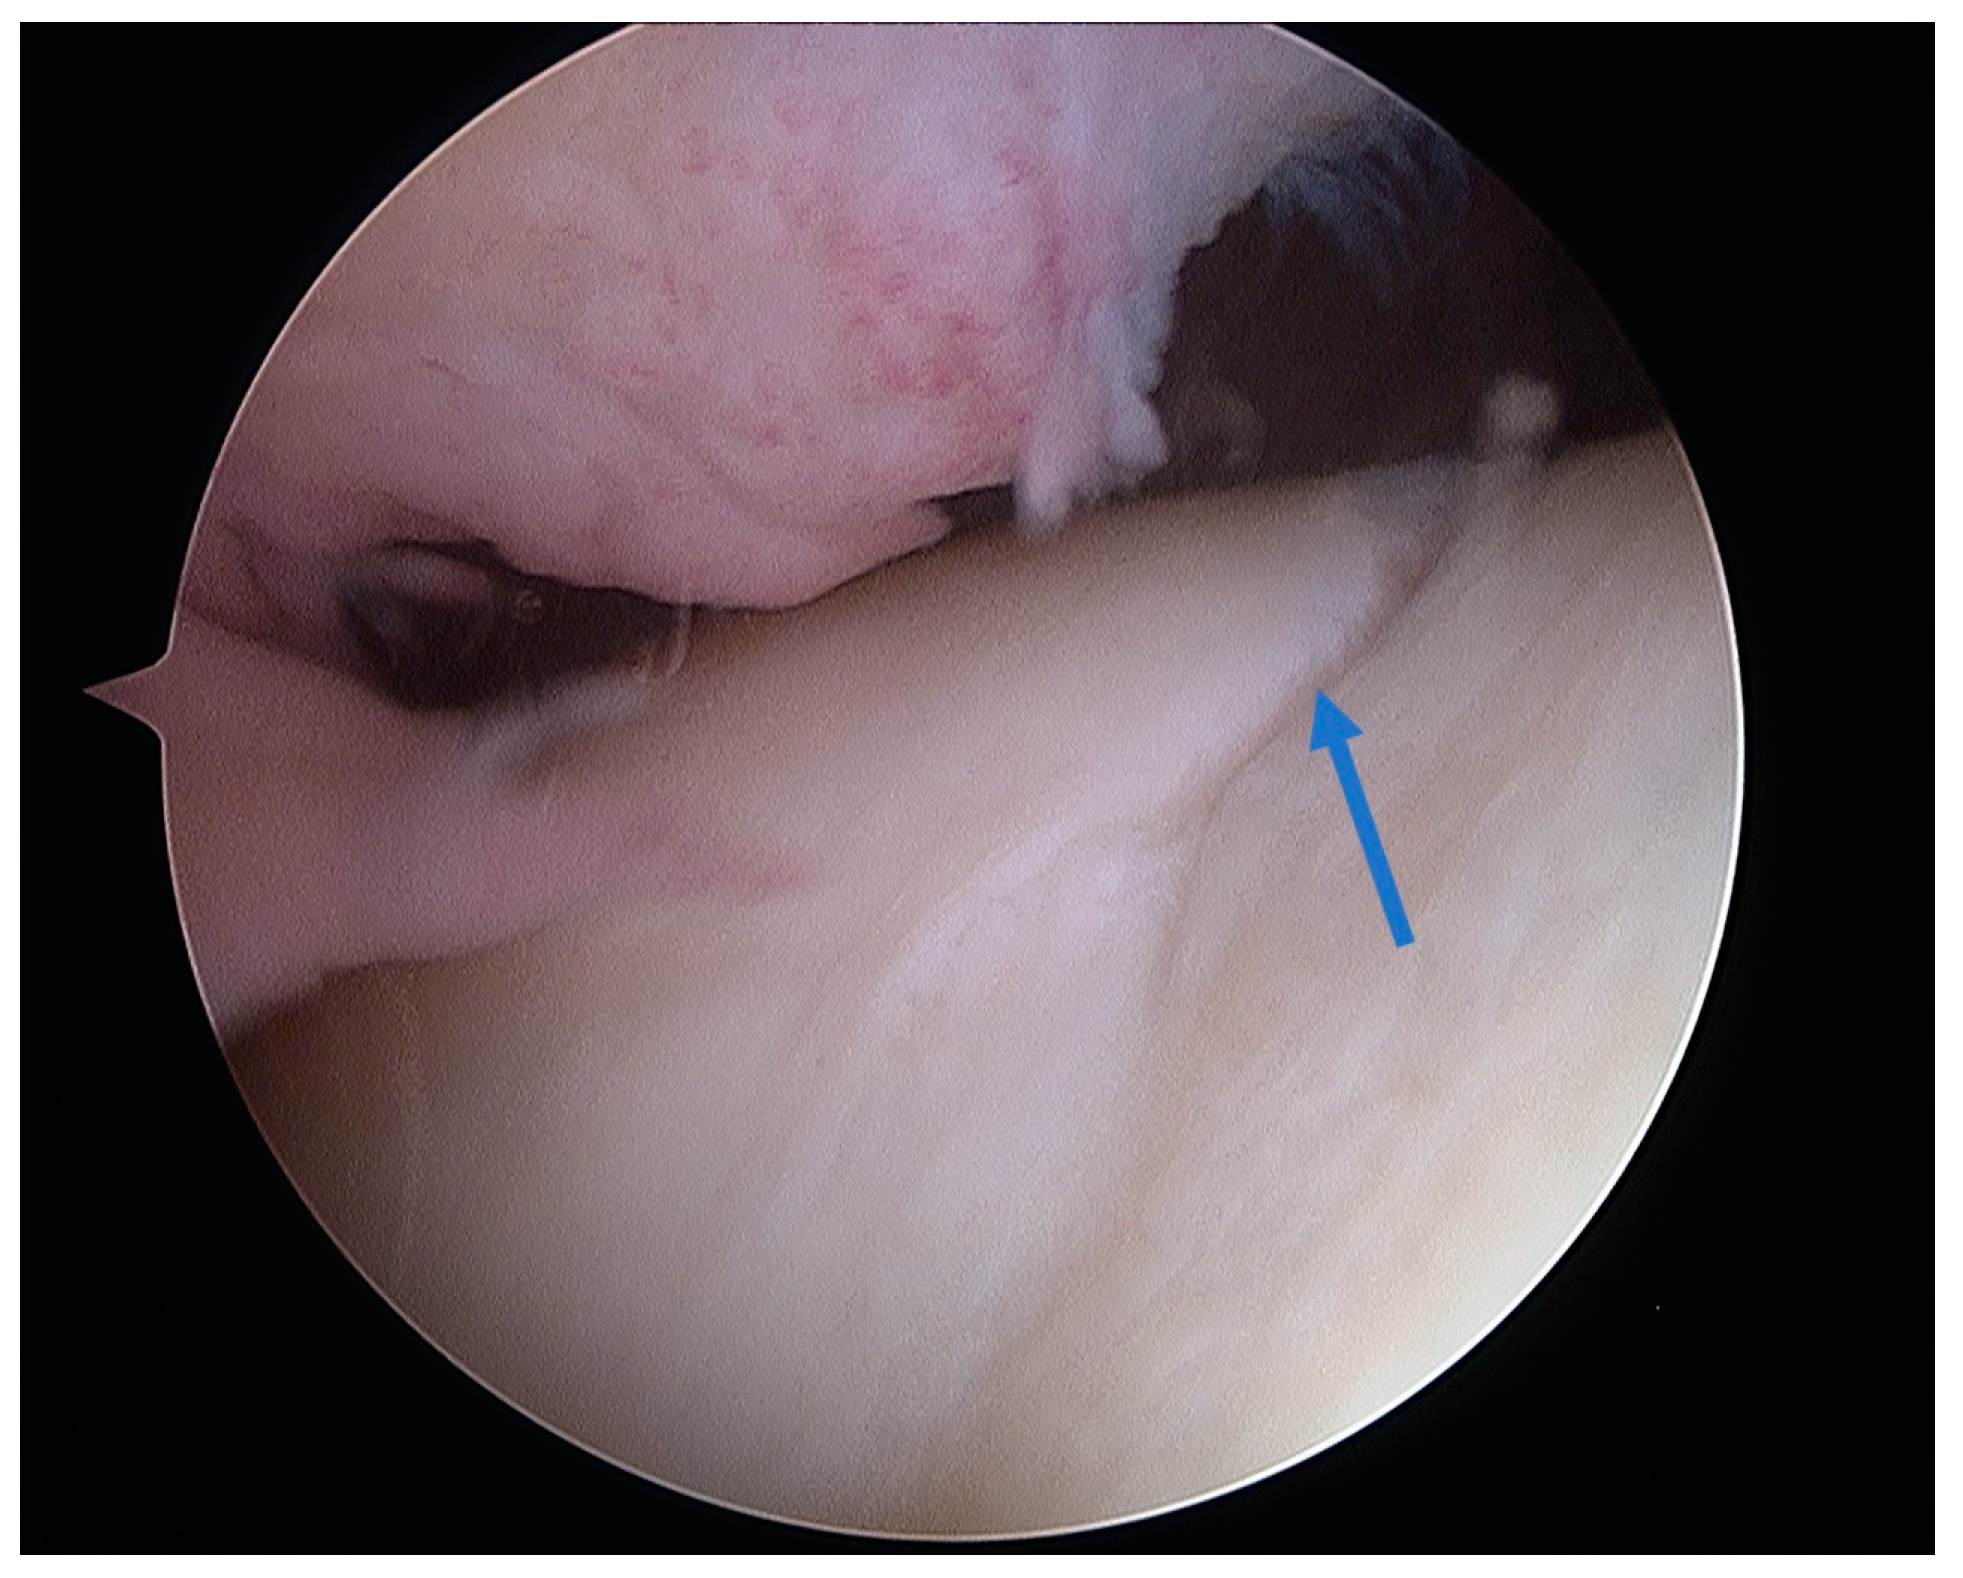

5.3. Osteochondral Autograft Transfer System (OATS)